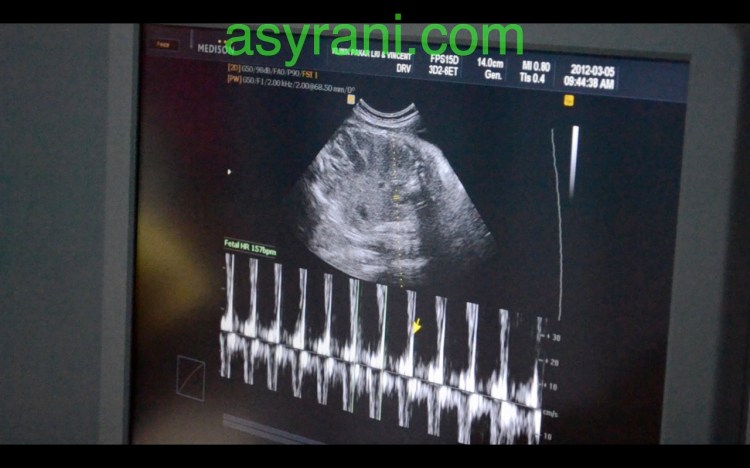

Denyutan Jantung yang optimum iaitu 157